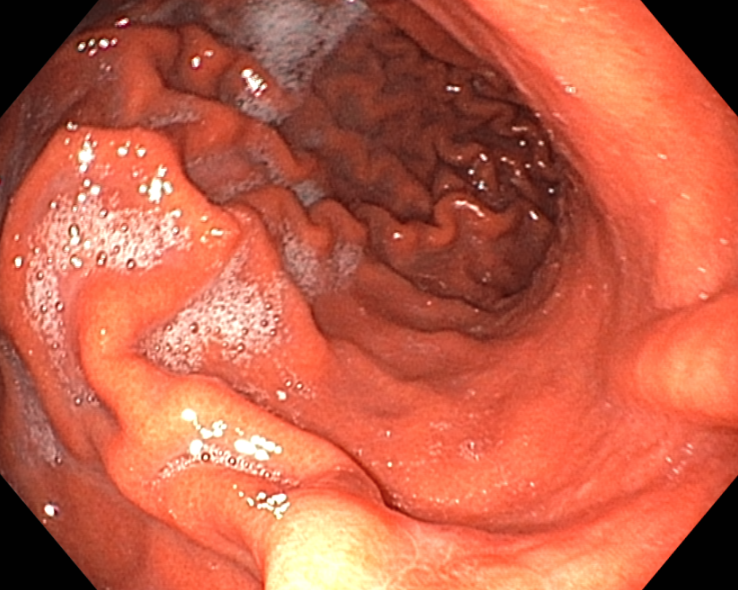

다음은 위내시경에서 확인된 위분문부와 유문부 점막에 생긴 급성위점막병변 사진입니다.

치료 8일 후 추적 위내시경을 시행하였습니다. 모두 호전된 소견.